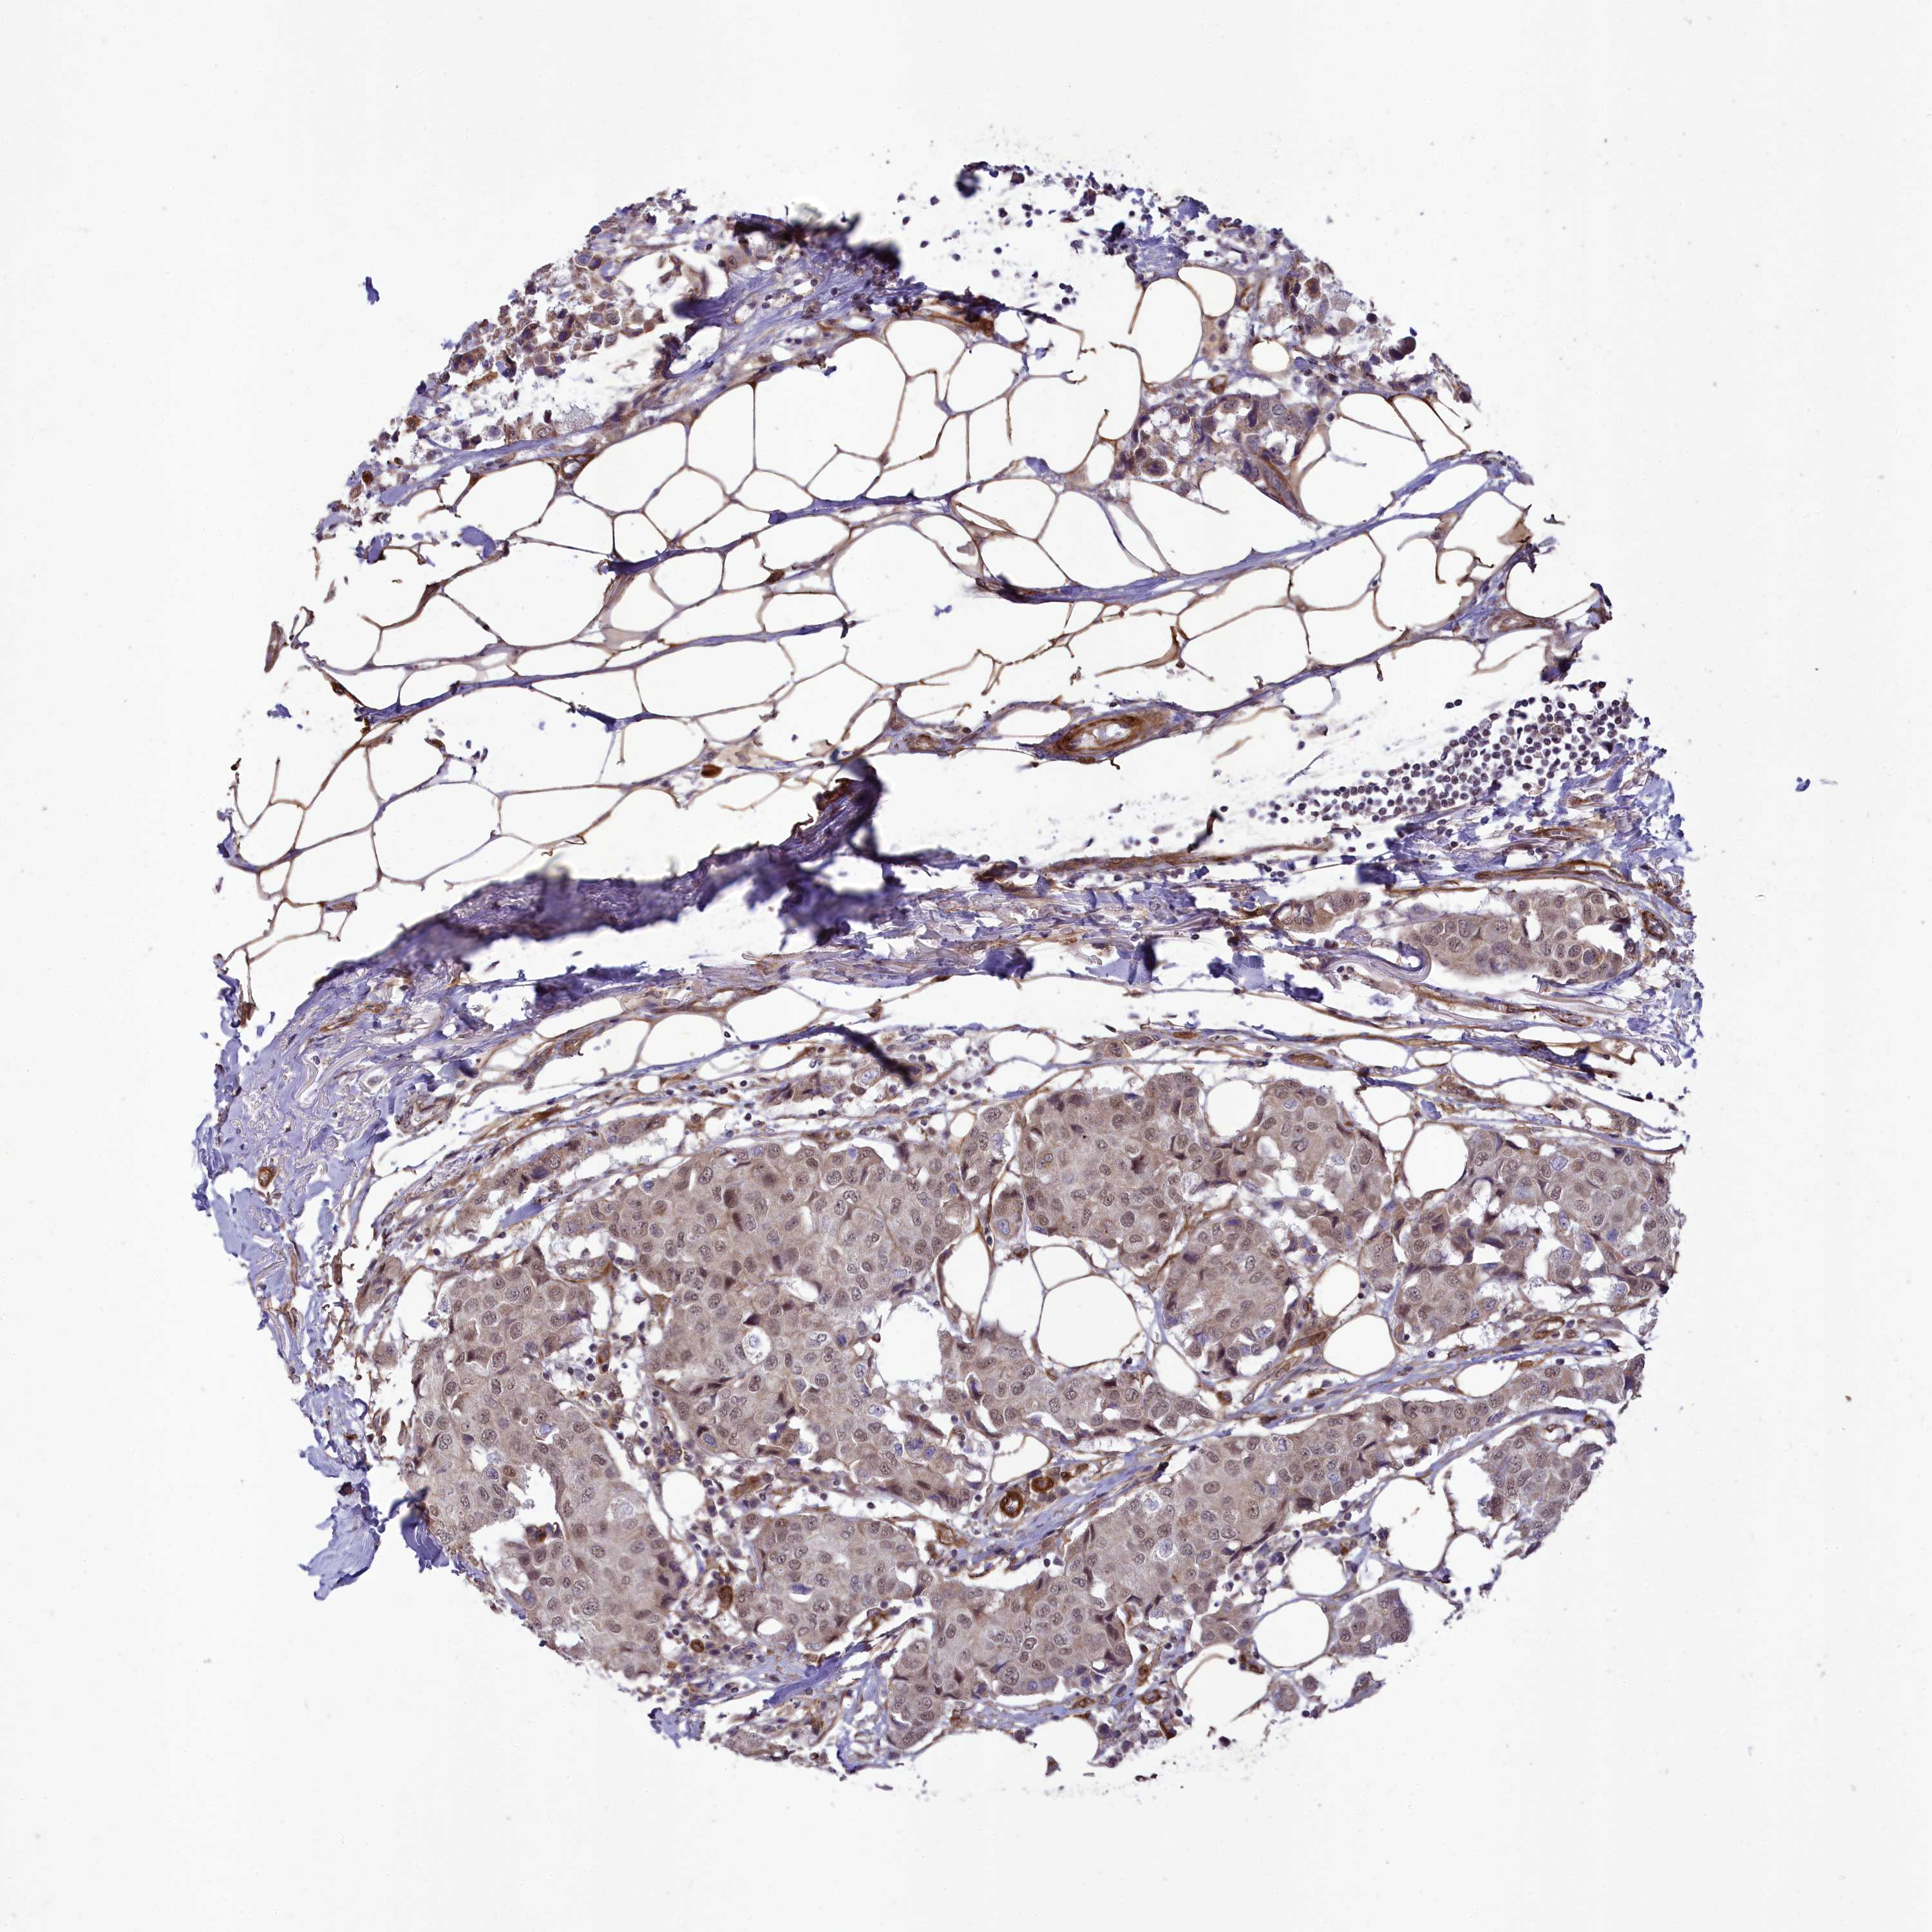

CANCER BREAST CANCER Show tissue menu

BRCA TCGA BRCA VALIDATION PROTEIN EXPRESSION